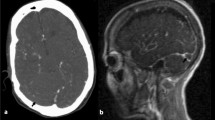

Leach, J. L., Fortuna, R. B., Jones, B. V. & Gaskill-Shipley, M. F. Imaging of cerebral venous thrombosis: current techniques, spectrum of findings, and diagnostic pitfalls. Radiographics 26 (Suppl. 1), S19–S41 (2006).

Roland, T. et al. Unenhanced brain CT is useful to decide on further imaging in suspected venous sinus thrombosis. Clin. Radiol. 65, 34–39 (2010).

Buyck, P. J. et al. CT density measurement and H:H ratio are useful in diagnosing acute cerebral venous sinus thrombosis. AJNR Am. J. Neuroradiol. 34, 1568–1572 (2013).

Virapongse, C., Cazenave, C., Quisling, R., Sarwar, M. & Hunter, S. The empty delta sign: frequency and significance in 76 cases of dural sinus thrombosis. Radiology 162, 779–785 (1987).